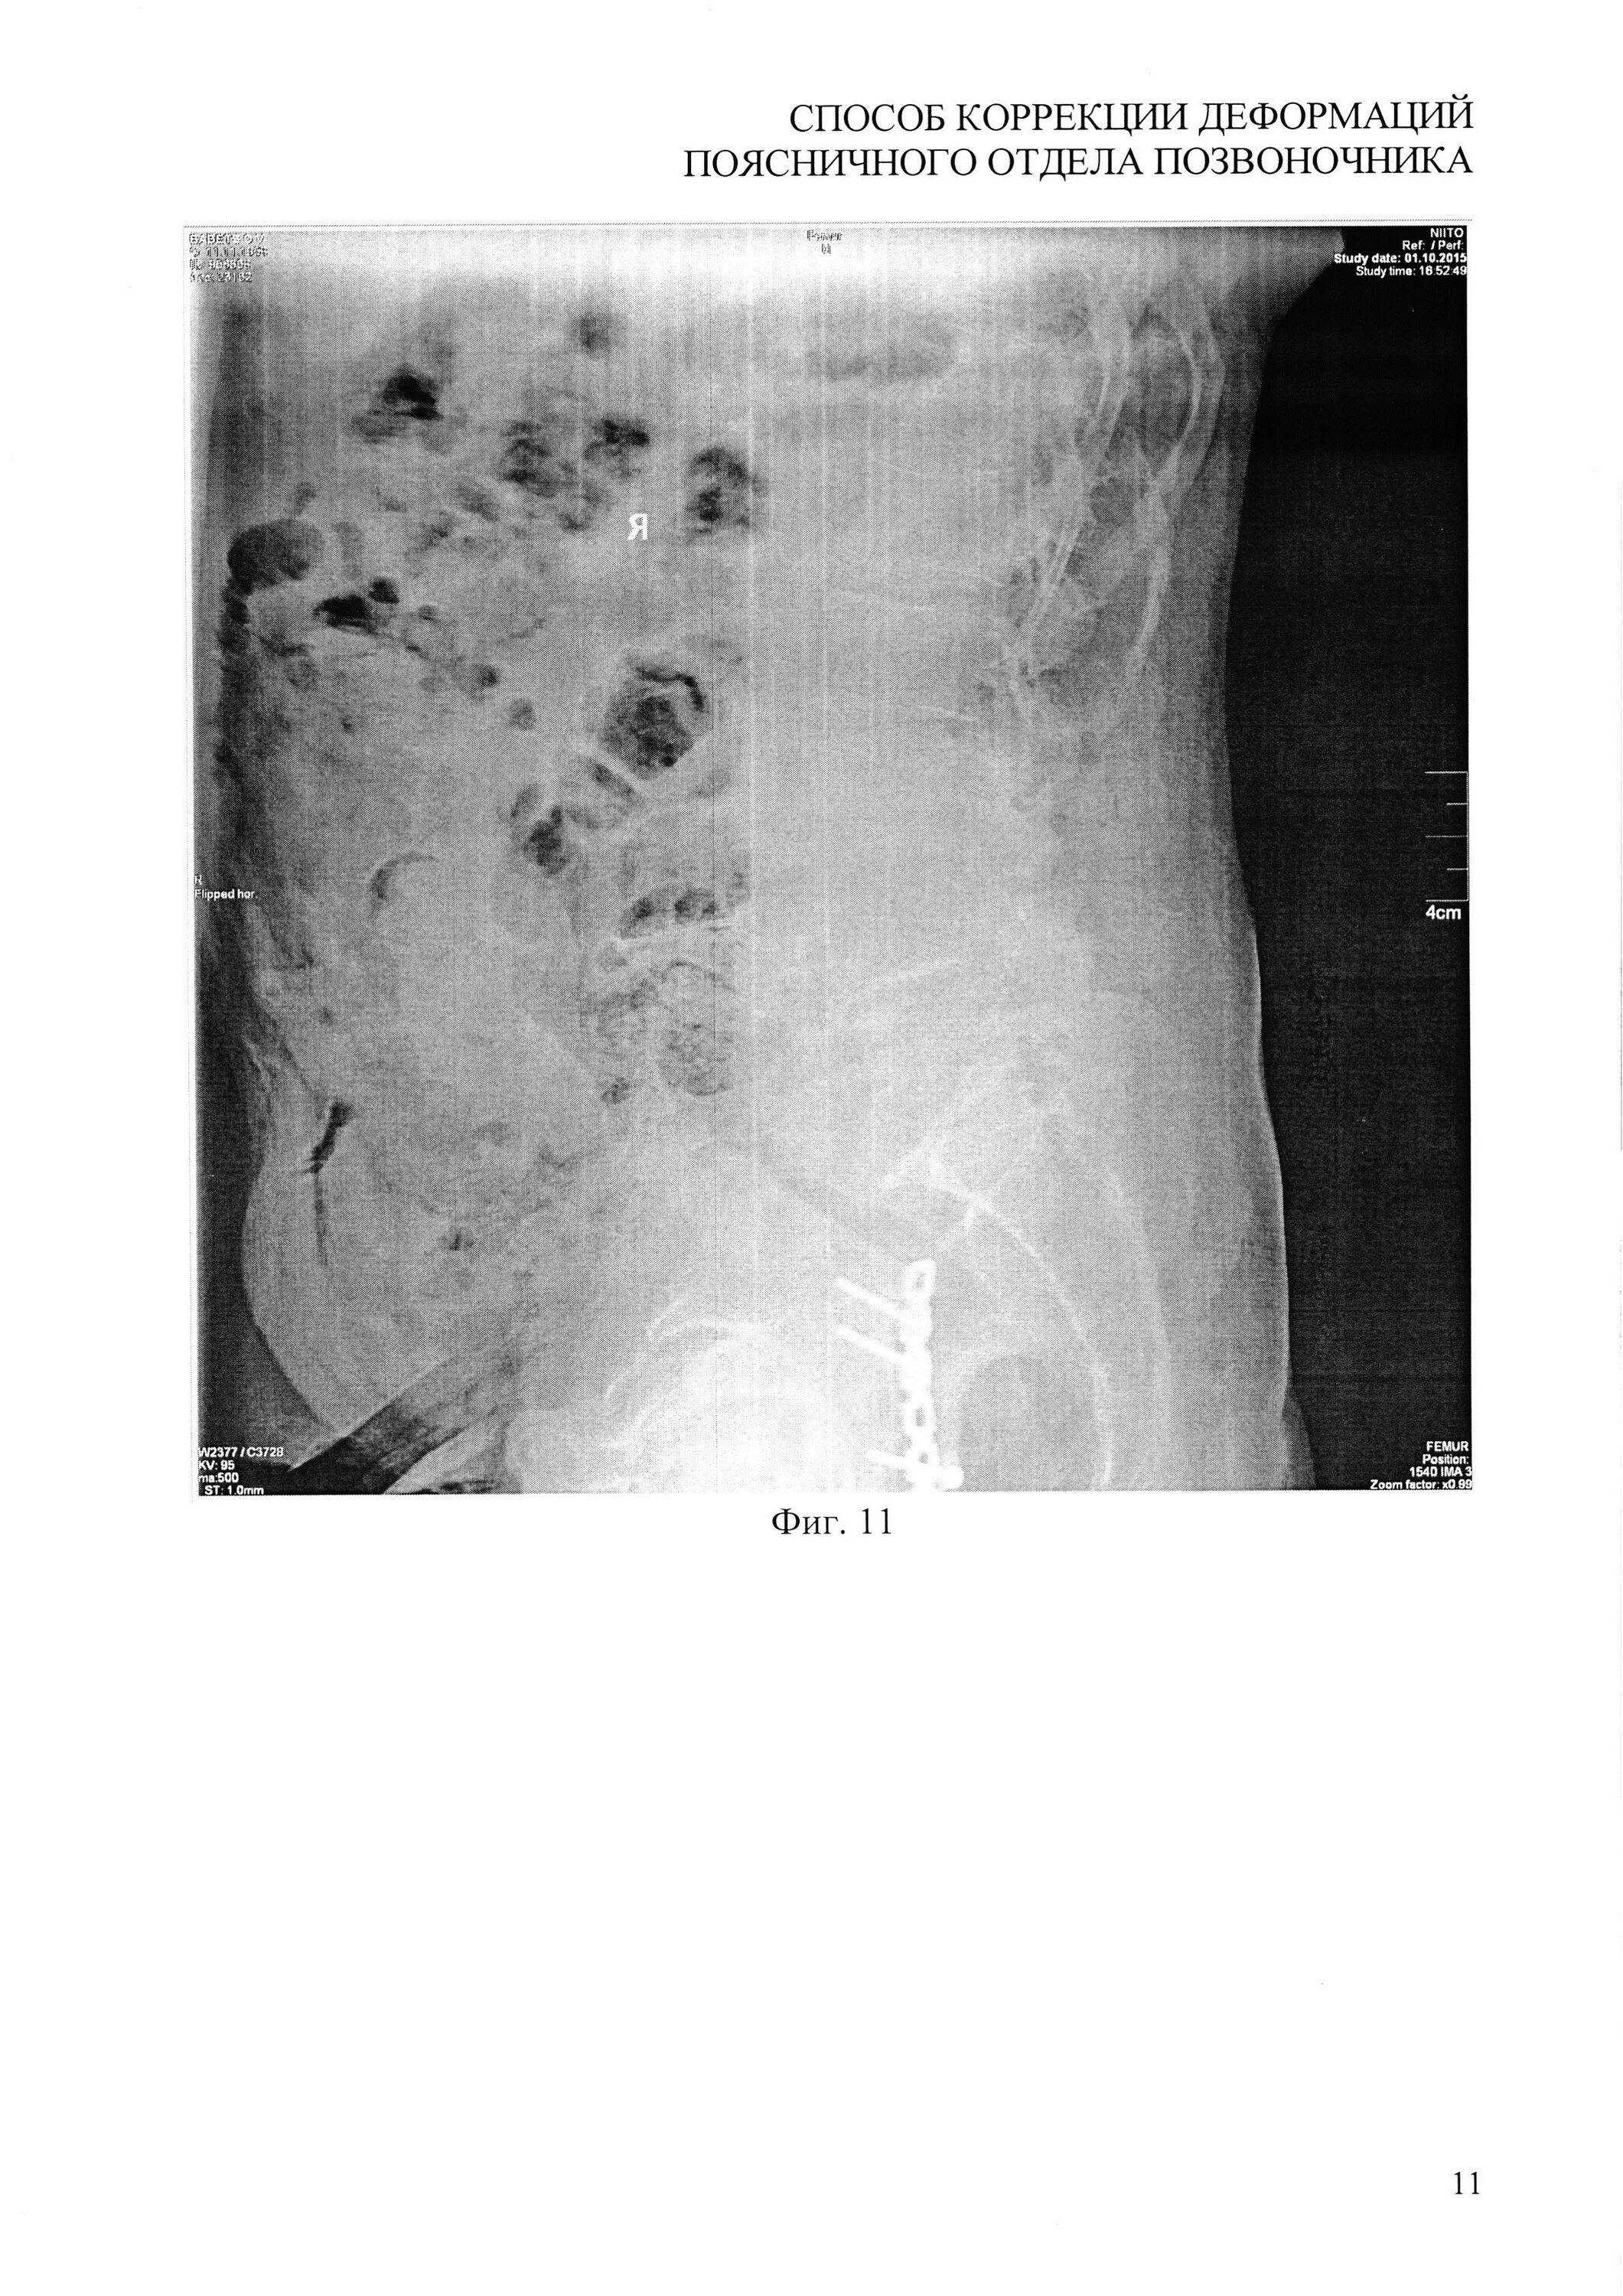

Грыжа деформирует дуральный мешок